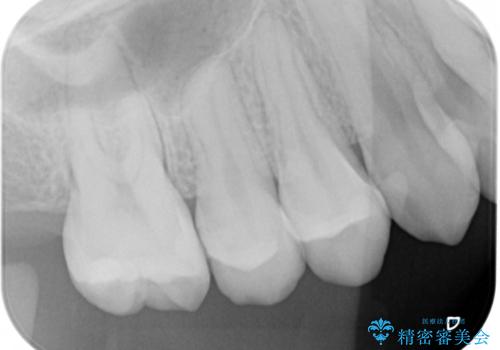

- 以前虫歯になり保険でプラスチックの詰め物をした部分の変色を主訴に、やり直しのご依頼を頂きました。

虫歯になった範囲が大きくなってくると削る範囲も比例して大きくなります。ある一定以上の大きさや範囲になった時の治療法に「インレー」というものがあり、保険の範囲では銀歯かプラスチック(適用条件有り)が、自費ではセラミックやゴールドといった素材を選ぶことができます。

セラミックやゴールドは、素材自体の劣化が非常に少なく精度も高いため、治療費はかかりますが、やり直しになる可能性を限りなく低くすることができます。